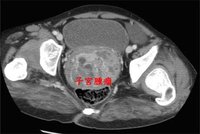

陰超,也就是陰道B超,又稱腔內B超,是將B超探頭放入 陰道或者 直腸進行 超聲診斷的方法,特別適合於觀察小 骨盆內的 盆腔臟器。與腹部B超相比,陰超的圖像更加清晰逼真、結果更準確,而且被檢者也不用“ 憋尿”。特別適合於 排卵監測、 宮外孕的確診、子宮占位性疾病以及 多囊卵巢綜合症和 朱古力囊腫的診斷。對於有過性生活的檢查者可以通過 陰道檢查,對於 處女可以通過直腸進行B超檢查。

月經周期子宮內膜一、正常月經周期子宮內膜聲像圖表現及正常卵巢內成熟與未成熟卵泡(所謂“測排卵”)。 二、子宮良性腫瘤:1、子宮腺肌病; 2、子宮肌瘤。 三、子宮惡性腫瘤:1、子宮內膜癌 ;2、子宮頸癌。 四、卵巢非贅生性囊腫:1、多囊腫卵巢綜合症; 2、朱古力囊腫。 五、卵巢腫瘤。 六、儘早明確診斷早期妊娠。 七、異常早期妊娠特別是異位妊娠(即“宮外孕”),由於宮外孕是臨床急症,搶救不及時亦 致死亡